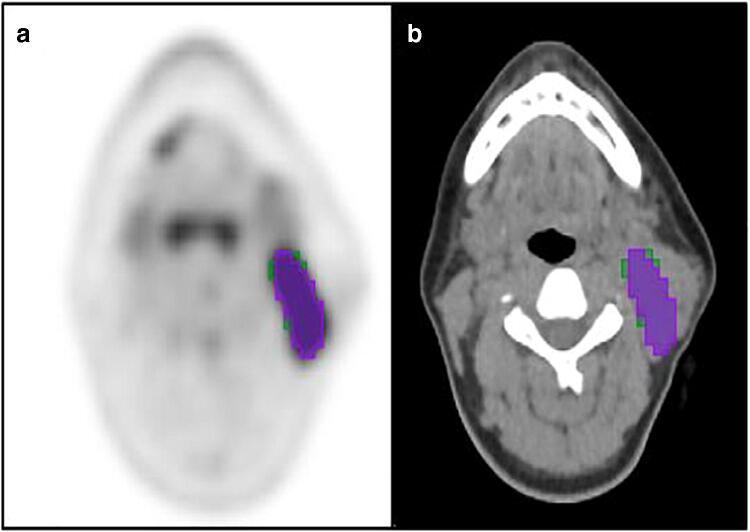

All cHL patients undergoing pre-treatment PET/CT at our institution between 2008 and 2018 were retrospectively identified. A 1.5 × mean liver standardised uptake value (SUV) and a fixed 4.0 SUV threshold were used to segment PET/CT data. Feature extraction was performed using PyRadiomics with ComBat harmonisation. Training (80%) and test (20%) cohorts stratified around 2-year event-free survival (EFS), age, sex, ethnicity and disease stage were defined. Seven ML models were trained and hyperparameters tuned using stratified 5-fold cross-validation. Area under the curve (AUC) from receiver operator characteristic analysis was used to assess performance.

方法

回顾性分析了 2008 年至 2018 年期间在我院接受治疗前 PET/CT 的所有 cHL 患者。使用 1.5×平均肝脏标准化摄取值(SUV)和固定的 4.0 SUV 阈值对 PET/CT 数据进行分割。使用 PyRadiomics 结合 ComBat 均衡化进行特征提取。根据 2 年无事件生存(EFS)、年龄、性别、种族和疾病分期,将患者分为训练(80%)和测试(20%)队列。使用分层 5 折交叉验证训练和调优 7 个 ML 模型。使用受试者工作特征分析的曲线下面积(AUC)评估性能。